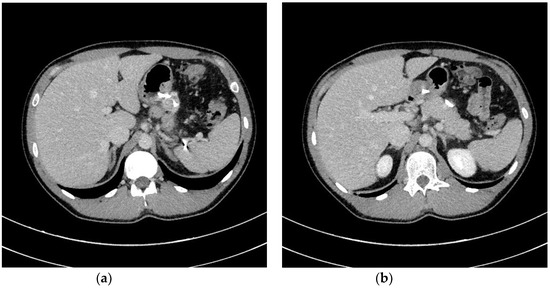

| Transmural endoscopic drainage with use of SEMSs | Active (with nasal drain) or passive (without nasal drain) transmural drainage accomplished via insertion of metal stent (SEMS) through the transmural fistula into lumen of necrotic collection. Indications for this type of drainage are extensive WOPN containing poorly-liquefied necrotic tissues, in which endoscopic necrosectomy may be necessary in the next step. SEMSs are usually used in the endoscopic treatment of WOPN up to sixth week from the beginning of ANP. |

| Endoscopic necrosectomy under fluoroscopic guidance (endoscopic debridement) | Procedure that enable to remove necrotic tissues from necrotic cavity through transmural fistula under fluoroscopy with use of various types of endoscopic tools. Indication for endoscopic debridement is WOPN containing poorly-liquefied necrotic tissues. |

| Direct endoscopic necrosectomy | Procedure accomplished via insertion of endoscope through the transmural fistula into the lumen of WOPN and direct removal of necrotic tissues under endoscopic view with use of different types of endoscopic tools. Direct endoscopic necrosectomy is usually technically easier to proceed during transmural drainage with use of SEMSs. Indications for direct endoscopic necrosectomy are extensive WOPN containing poorly-liquefied necrotic tissues without clinical improvement despite active transmural drainage. |